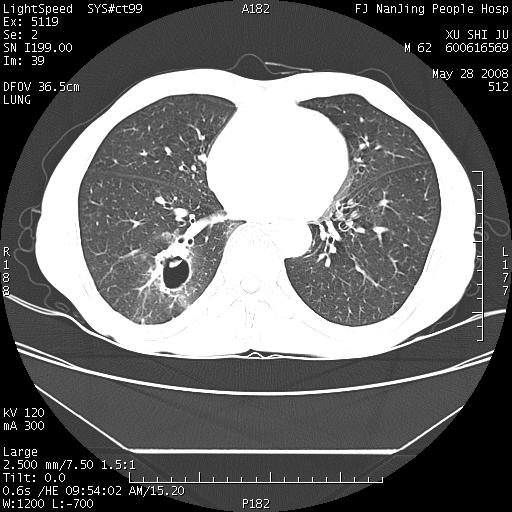

以下是引用杀毒软件在2008-5-28 19:16:00的发言:[br]病灶旁“晕轮征”,考虑肺真菌病

以下是引用qiushi在2008-5-28 20:01:00的发言:[br]空洞周围环状磨玻璃影(日晕征),考虑肺曲霉菌病.

以下是引用yuhongjun在2008-5-29 4:28:00的发言:[br]空洞周围环状磨玻璃影(日晕征),考虑肺曲霉菌病。支持! [br] [br]

以下是引用lrj在2008-5-28 21:10:00的发言:[br]所示应该是正常结构,是对称的,多个层面都有!也不像是内乳动脉或是肿大淋巴结![br]右下肺渗出性病变伴空洞形成,其洞内见一结节,以下诊断都有可能:1 右下肺曲菌感染, 2右下肺结核空洞形成伴曲菌感染!3右下肺结核空洞伴壁内占位形成,虽说后者发生的几率很低 但作为我们应该多考虑一下吧!最重要的结合临床